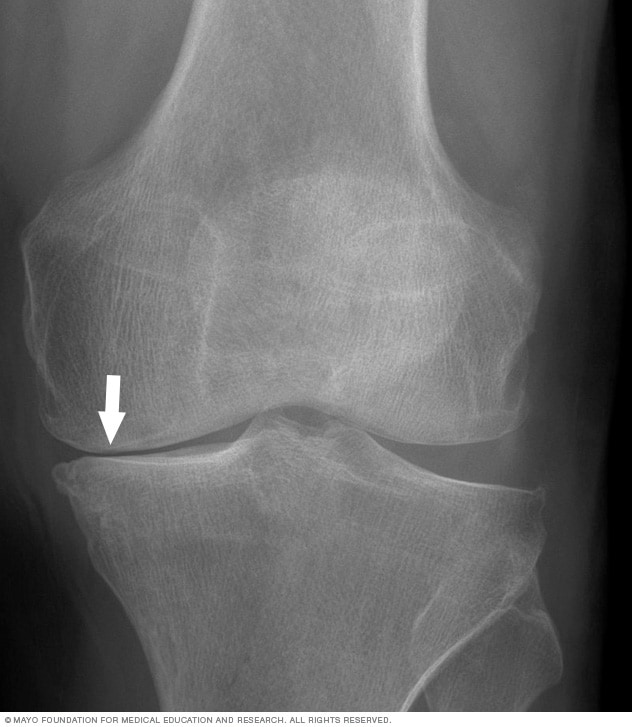

- Deepvein thrombosis (DVT): A clot forms in a deep vein, often the calf, and blocks flow.